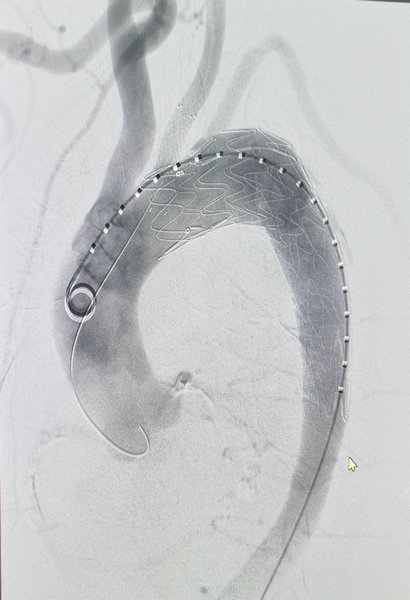

造影显示覆膜支架及颈总动脉支架已成功释放